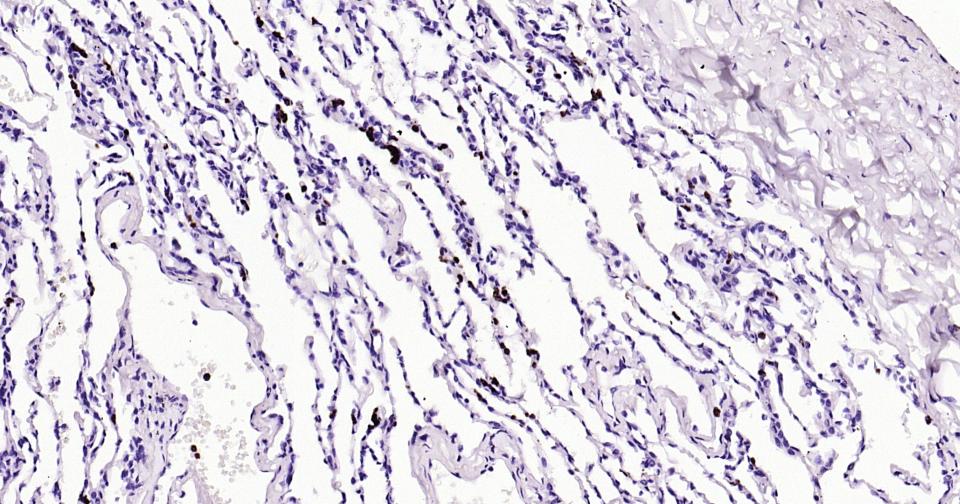

Cytolytic T lymphocytes (CTL) and natural killer (NK) cells share the remarkable ability to recognize, bind, and lyse specific target cells. They are thought to protect their host by lysing cells bearing on their surface 'nonself' antigens, usually peptides or proteins resulting from infection by intracellular pathogens. The protein encoded by this gene is crucial for the rapid induction of target cell apoptosis by CTL in cell-mediated immune response. [provided by RefSeq, Jul 2008]

| IHC-P | Human | 1:200-1000 | |